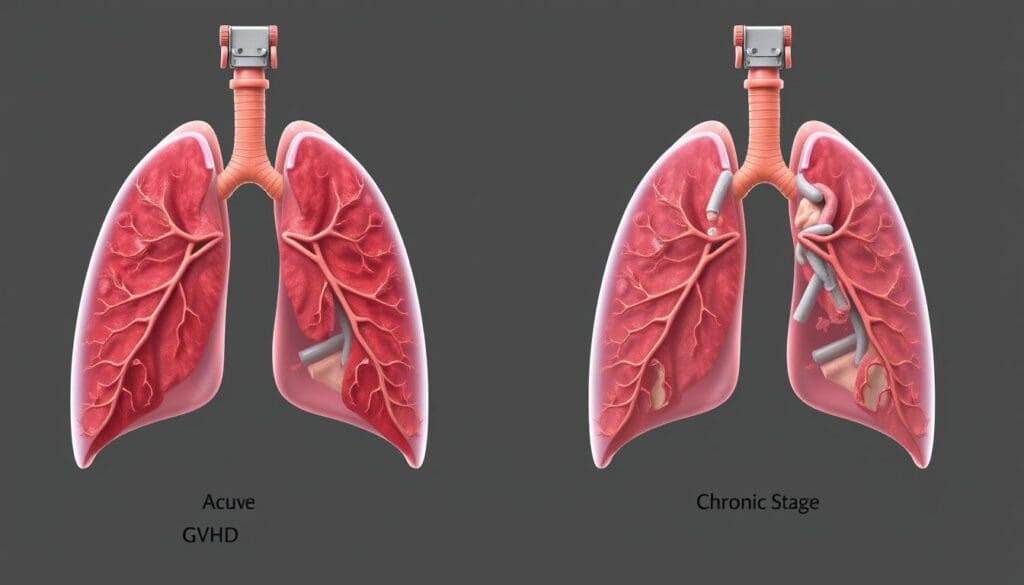

Fact 1: Acute vs. Chronic Pulmonary GVHD Present Differently

It’s important to know the difference between acute and chronic pulmonary GVHD. GVHD lung symptoms change based on the type, affecting how we treat pulmonary GVHD.

Acute GVHD happens in the first 100 days after a transplant. It’s marked by a strong immune reaction. In the lungs, it can cause cough, trouble breathing, and fever.

Acute Lung GVHD Manifestations

Acute lung GVHD can be hard to spot because its symptoms are not always clear. “It can look like other lung problems, like infections or idiopathic pneumonia syndrome,” says a doctor. This makes it key to watch for it in transplant patients.

Chronic Lung GVHD Characteristics

Chronic GVHD starts after 100 days post-transplant and can affect many parts of the body, including the lungs. It shows up slowly, with symptoms like getting worse breathing and lung blockages.

A doctor notes, “Chronic GVHD can cause a lot of problems, with bronchiolitis obliterans syndrome being a big issue in lung health.”

Knowing these differences helps us manage pulmonary GVHD better and improve patient care.